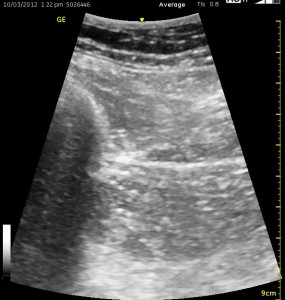

The image above is not an obvious one, and I did that on purpose. You have to get used to the idea that you will not always have a ‘super distinct’ image with this approach, and you will often need to use a number of additional clues to find your target and then to put local around it. I think the only way to really get a handle on being able to identify the basic elements is to look at several images over and over, so I have provided several below for you to use for practice. Note that the sciatic nerve will ‘poke out’ from behind the femur to different degrees depending on your orientation to the femur as well as to how far up or down the femur you go. It will be seen more if you are proximal. See how well you can identify the structures in the images below.